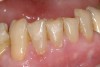

Figure  3  Severe dental erosion and attrition in a GERD patient.

Figure 3

Characteristics of damage to tooth structures caused by acidity include wear on the occlusal surfaces of molars and a saucer shape on the cusps of molars (perimolysis).12 The erosion can vary from minor and subtle changes on the tooth surface, ie, loss of luster, a dull or matted look, to cupping on occlusal surfaces or incisal edges, which may extend to dentin. Usually, the erosive lesions demonstrate greater width than depth. When combined with abrasive forces or stresses, the tooth surface loss may occur at a faster rate (Figure 2, Figure 3, Figure 4 and Figure 5).